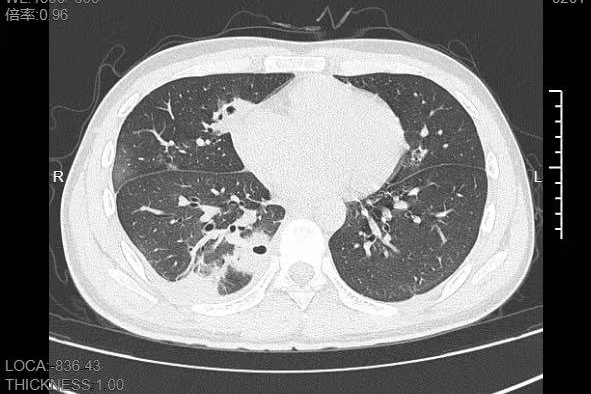

熬到第三天,小林已经烧到39℃,赶紧来到宁波大学附属第一医院就诊。接诊的呼吸与危重症医学科丁群力主任医师一看他的症状,立刻安排了CT检查。结果显示:小林的肺里有十几个空洞,部分肺组织已经坏死,这是典型的血源性肺脓肿。

像小林这样,当细菌跑到肺组织上后,就会开始疯狂破坏肺细胞,引发局部炎症。随着炎症加重,肺组织会逐渐坏死、液化,最终形成一个个空洞。

如果没有及时就医,风险还会持续升级,轻则导致肺脓腔破裂,引发脓胸、脓气胸,胸腔里积满脓液,重则细菌会再次扩散到肝脏、心脏等关键器官,甚至引发脓毒症休克,危及生命。

即便最终治愈,严重的肺组织坏死也可能留下后遗症,比如肺功能下降,影响后续的正常呼吸。